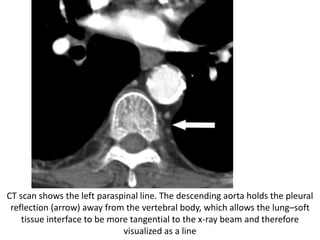

CT scan shows the left paraspinal line. The descending aorta holds the pleural

reflection (arrow) away from the vertebral body, which allows the lung–soft

tissue interface to be more tangential to the x-ray beam and therefore

visualized as a line